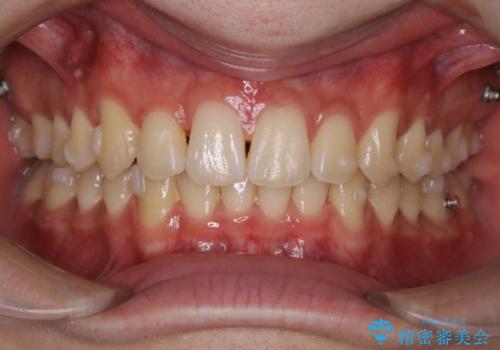

インビザライン:前歯のがたつきと噛み合わせの治療

- 前歯のがたつきが気になるとご相談にいらした方です。左の奥歯の噛み合わせのズレも認められたため、インビザライン治療にて改善しました。

主訴である前歯のガタつきだけでなく、奥歯の噛み合わせからしっかり治療したため、治療期間が長めとなりました。患者様ご本人としては治療の途中で一時的にモチベーションが下がったこともあったようですが、最後まで頑張って続けて頂けたことで噛み合わせ及び見た目の改善を行うことが出来ました。